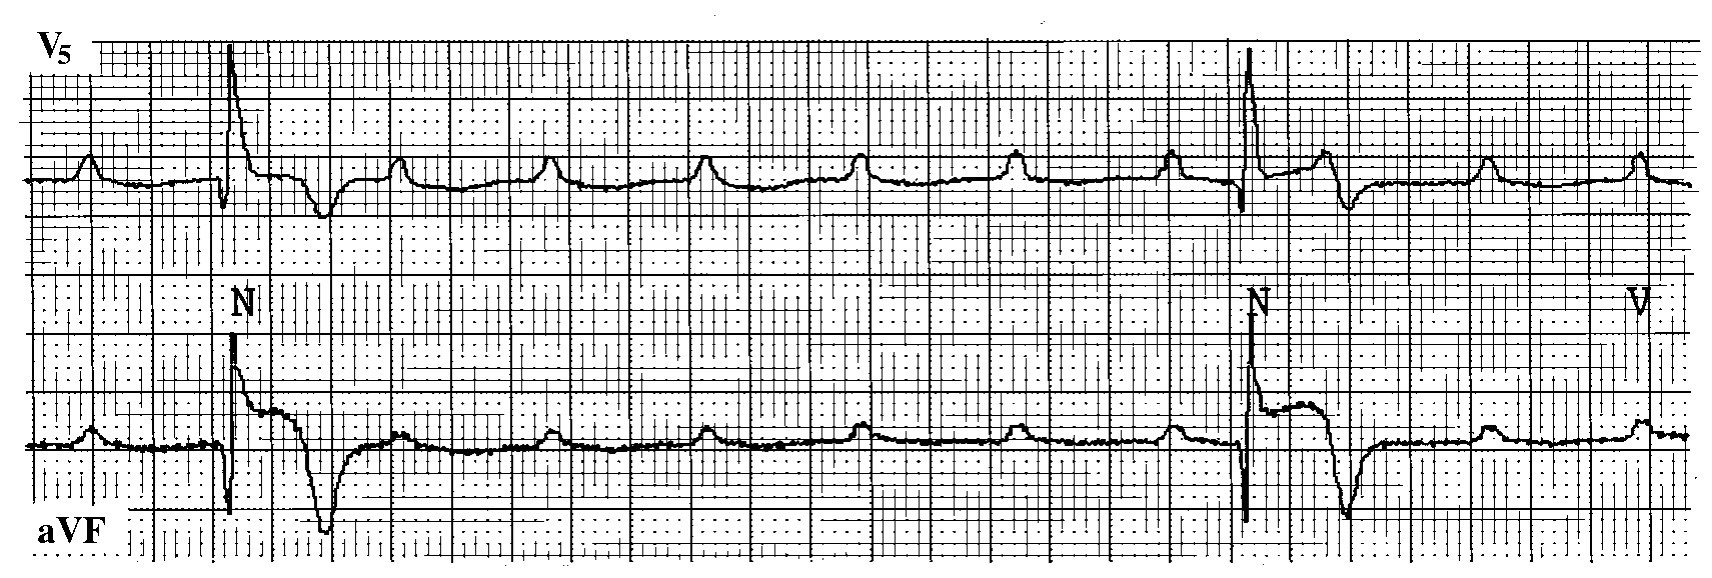

(3)P波上室性期前收缩 即舒张期、长联律间距、R落在P波上的室性期前收缩,又称RonP型室性期前收缩。其在1974年由Desoyza等人提出,后被其他学者所证实,甚至认为大多数室性心动过速是由RonP型室性期前收缩引起。其诱发室性心动过速的发生率高于RonT型,发生机制不明,可能与P波后心房收缩对心室牵拉形成机械—电反馈性折返所致。特别是当心肌缺血复极延长或伴有低血钾时,更易发生心室快速反应。P上室性期前收缩在心肌梗死急性期具有相当的危险性(图12-34)。

img244

图12-34 P上型室性期前收缩

患者女性,60岁,急性下壁心肌梗死合并室性心律失常